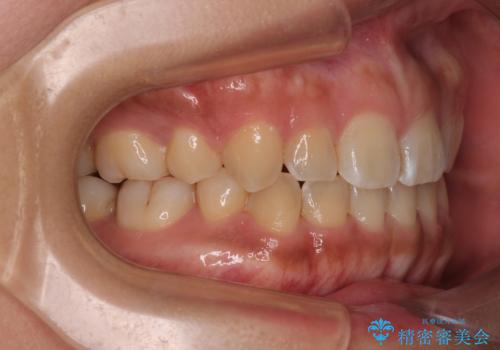

デコボコと捻れて前に飛び出した歯列 抜歯矯正でスッキリした口元に

- 前歯のデコボコと口元の突出感を気にして来院された患者様です。

非抜歯矯正ではデコボコを解消することでより口元が突出してしまうため、上下左右の小臼歯4本の抜歯を行い、ワイヤー装置による矯正治療を行うこととしました。

上顎小臼歯の歯根が左右ともに大きく曲がっており、スペースクローズに時間がかかってしまいました。